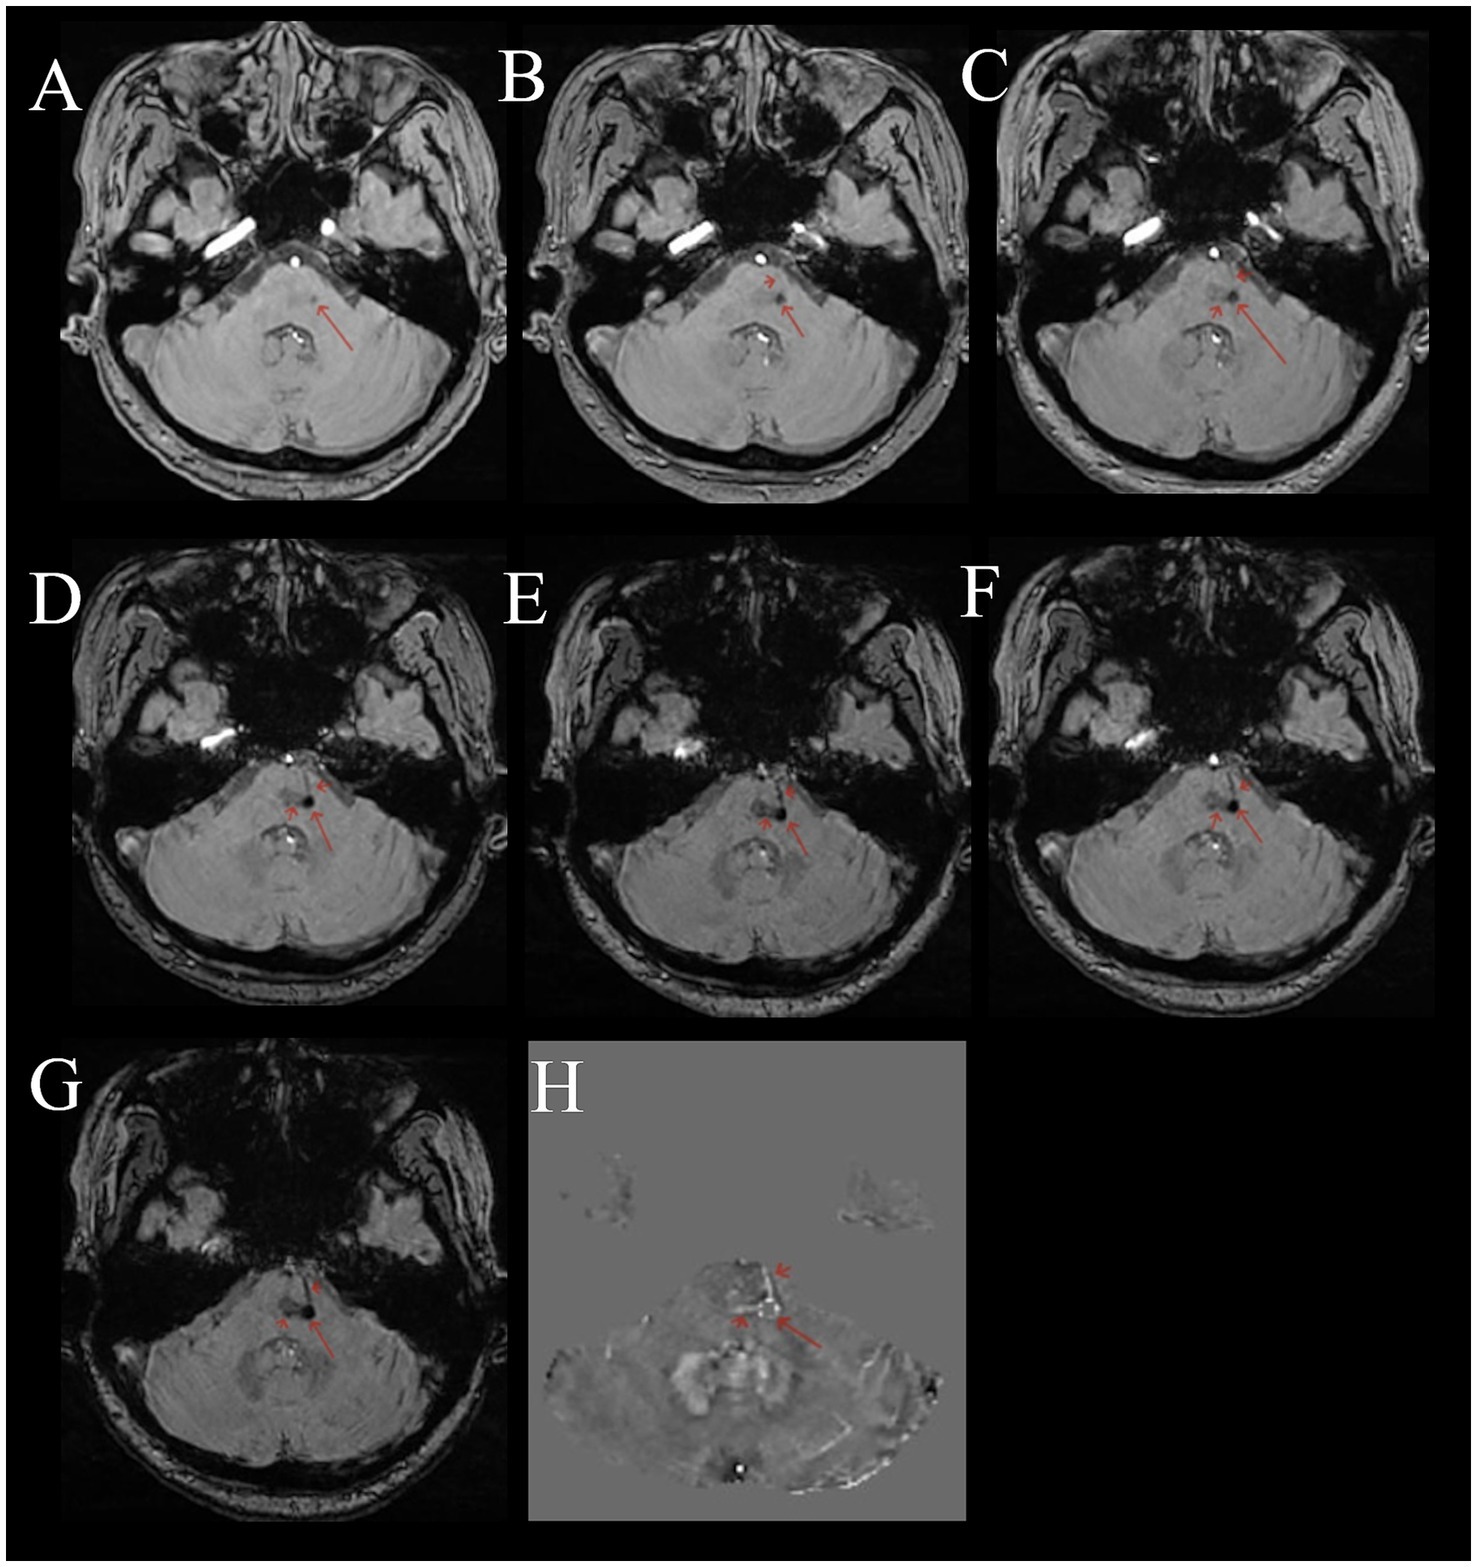

Compared to normal or other disease (see Supplementary material), on multi-echo SWI with long TE (22.5 ms), BCT lesions all presented as distinct small round hypointense signals on images, with punctate or strip-like slightly hyperintense signals at the center and a hypointense ring at the edge, forming a typical “single-ring target sign” (long red arrows in Figures 1A–D, 2A–G). Lesions had clear boundaries, and increased and thickened draining small veins were visible around the lesions (short red arrows in Figures 1A–D, 2A–G). QSM images showed round abnormal signals of lesions, with the central part being hyperintense due to the passage or penetration of central veins, a hypointense ring in the middle, and slightly hyperintense or hyperintense signals at the outermost edge, forming the most typical “double-ring target sign” (long red arrow in Figure 1E). The edges of some lesions showed a slightly hyperintense ring, and the inner side showed a hypointense ring, forming a typical “target sign” (dashed red arrow in Figure 1E). Meanwhile, increased and thickened small veins were observed around the lesions (short red arrows in Figures 1E, 2H). Some lesions only showed punctate hyperintense signals (solid long red arrow in Figure 1E). DWI, Flair, and T1WI images showed a few punctate hypointense signals (short red arrows in Figures 1F,H,I), and ADC showed punctate hyperintense signals (Figure 1G).

Figure 2

Female, 53 years old, with dizziness for 5 months. (A–G) Multi-echo QSM sequences with TE values of 3.3, 6.5, 9.7, 12.9, 16.1, 19.3, and 22.5 ms, respectively. (H) A QSM image. (A–G) Show a round low signal area in the pons (long red arrow). The surrounding area shows thickened, multiple draining veins with low signal (short red arrow). As the TE time increases, the lesion and draining veins become clearer. (H) Shows a disordered round signal in the pons (long red arrow), with surrounding draining veins showing high signal (short red arrow).

Comparison of the sensitivity of SWI and QSM map in detecting the central vein of BCT

The multi-echo SWI with long TE (22.5 ms) showed that among the 688 detected BCT lesions, 498 could display the central vein, with a positive rate of 72.4%. The QSM map detected 585 BCT lesions, among which 324 could display the central vein, with a positive rate of 55.4%. There was a difference in the detection rate of the central vein of BCT between the two sequences, and the multi-echo SWI sequence (TE 22.5 ms) was better than the QSM map ( = 39.937), (p < 0.001)) (Figure 2) (see Table 2).